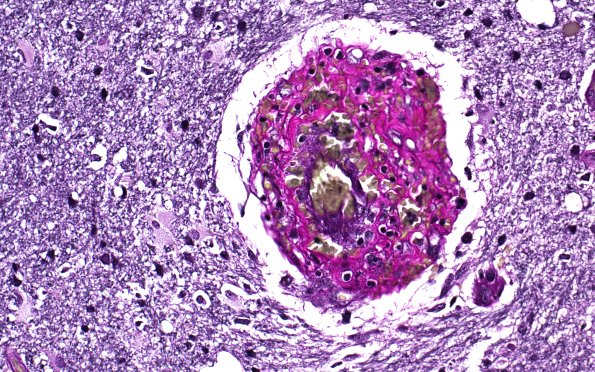

Washington University Experience | VASCULAR | Vasculitis - PACNS | 17C5 Vasculitis (Case 17) VVG 40X

The residua of an elastic lamina continues to be present but is surrounded by a cribriform fibrotic pattern. This is the same vessel as #17B3. (Elastin)